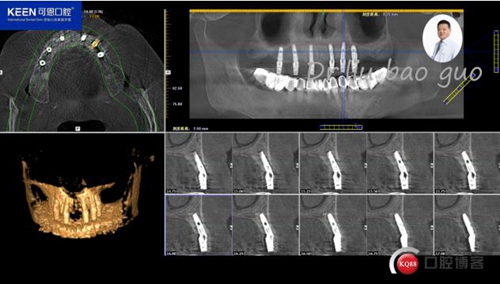

手術(shù)前種植軟件設(shè)計(jì)方案

術(shù)后照片